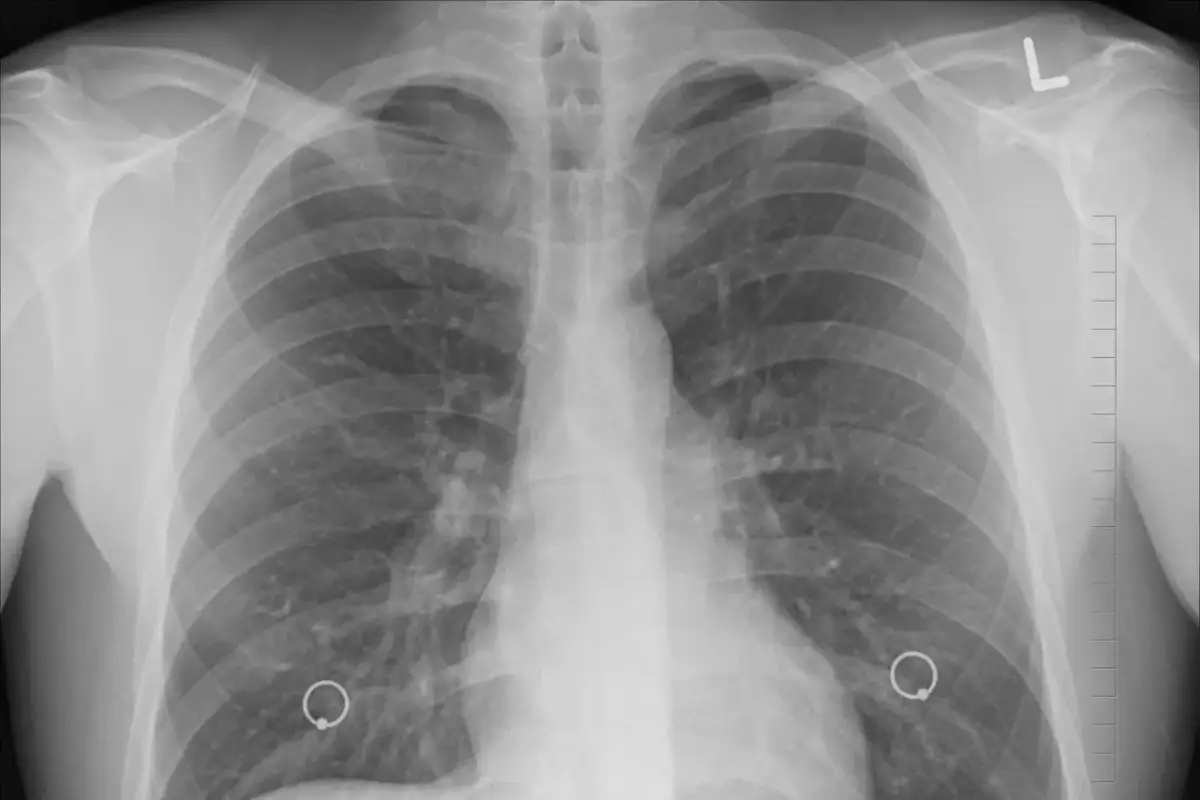

W medycynie, do oceny stopnia zaawansowania rozedmy płuc, a szerzej POChP, stosuje się międzynarodową klasyfikację GOLD (Global Initiative for Chronic Obstructive Lung Disease). Jest to standard, który pomaga lekarzom w diagnozowaniu, monitorowaniu i planowaniu leczenia. Kluczowym badaniem diagnostycznym w tej ocenie jest spirometria, która mierzy pojemność płuc i przepływ powietrza przez drogi oddechowe.

Najważniejszym wskaźnikiem spirometrycznym w kontekście rozedmy jest FEV1 (natężona objętość wydechowa pierwszosekundowa). Jest to objętość powietrza, którą pacjent jest w stanie wydmuchać z płuc w ciągu pierwszej sekundy maksymalnego wydechu. Wartość FEV1, wyrażona jako procent wartości należnej (czyli oczekiwanej dla osoby w danym wieku, płci i wzroście), mówi nam o stopniu zwężenia dróg oddechowych i uszkodzenia płuc. Im niższa wartość FEV1, tym bardziej zaawansowana jest rozedma.

Klasyfikacja GOLD wyróżnia cztery etapy ciężkości obturacji, oparte właśnie na wartości FEV1:

| Etap GOLD | Opis | Wartość FEV1 (wartości należnej) |

|---|---|---|

| GOLD 1 | Łagodny | ≥ 80% |

| GOLD 2 | Umiarkowany | 50–79% |

| GOLD 3 | Ciężki | 30–49% |

| GOLD 4 | Bardzo ciężki | < 30% |